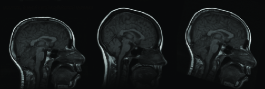

The algorithm is performed both on image scale and on standard intensity scale. Thirty deformed brain images are generated by applying random deformations to the original target images. Original source images are tried to be registered to each deformed target images on standard intensity scale and image scale. Random deformations are obtained by randomly choosing parameters for affine matrix A𝐴A. The resulting deformation field is normalized so that r.m.s displacement is at most 12 pixels. An example for affinely warped images is shown in Figure 6.

Figure 6: Images are randomly deformed by affine transformations

Refer to caption